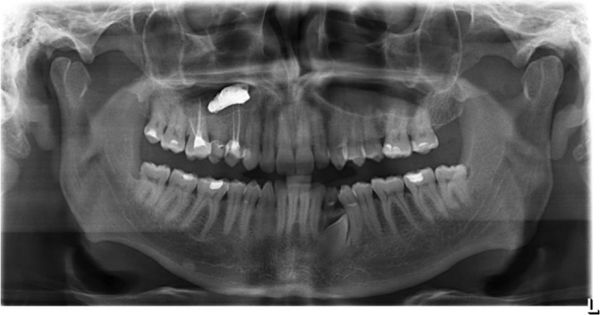

В основном мицетома гайморовой пазухи образуется тогда, когда через сообщающийся канал зуба в неё попадает пломбировочный материал. В состав пломбы входят оксид цинка и сульфат бария, образующие пищевую среду для аспергиллов, что провоцирует развитие мицетомы.

![Пломбировочный материал в гайморовой пазухе [15]](/pimg3/simptomi-blastomikoza-nosa-BE73C5.jpeg)